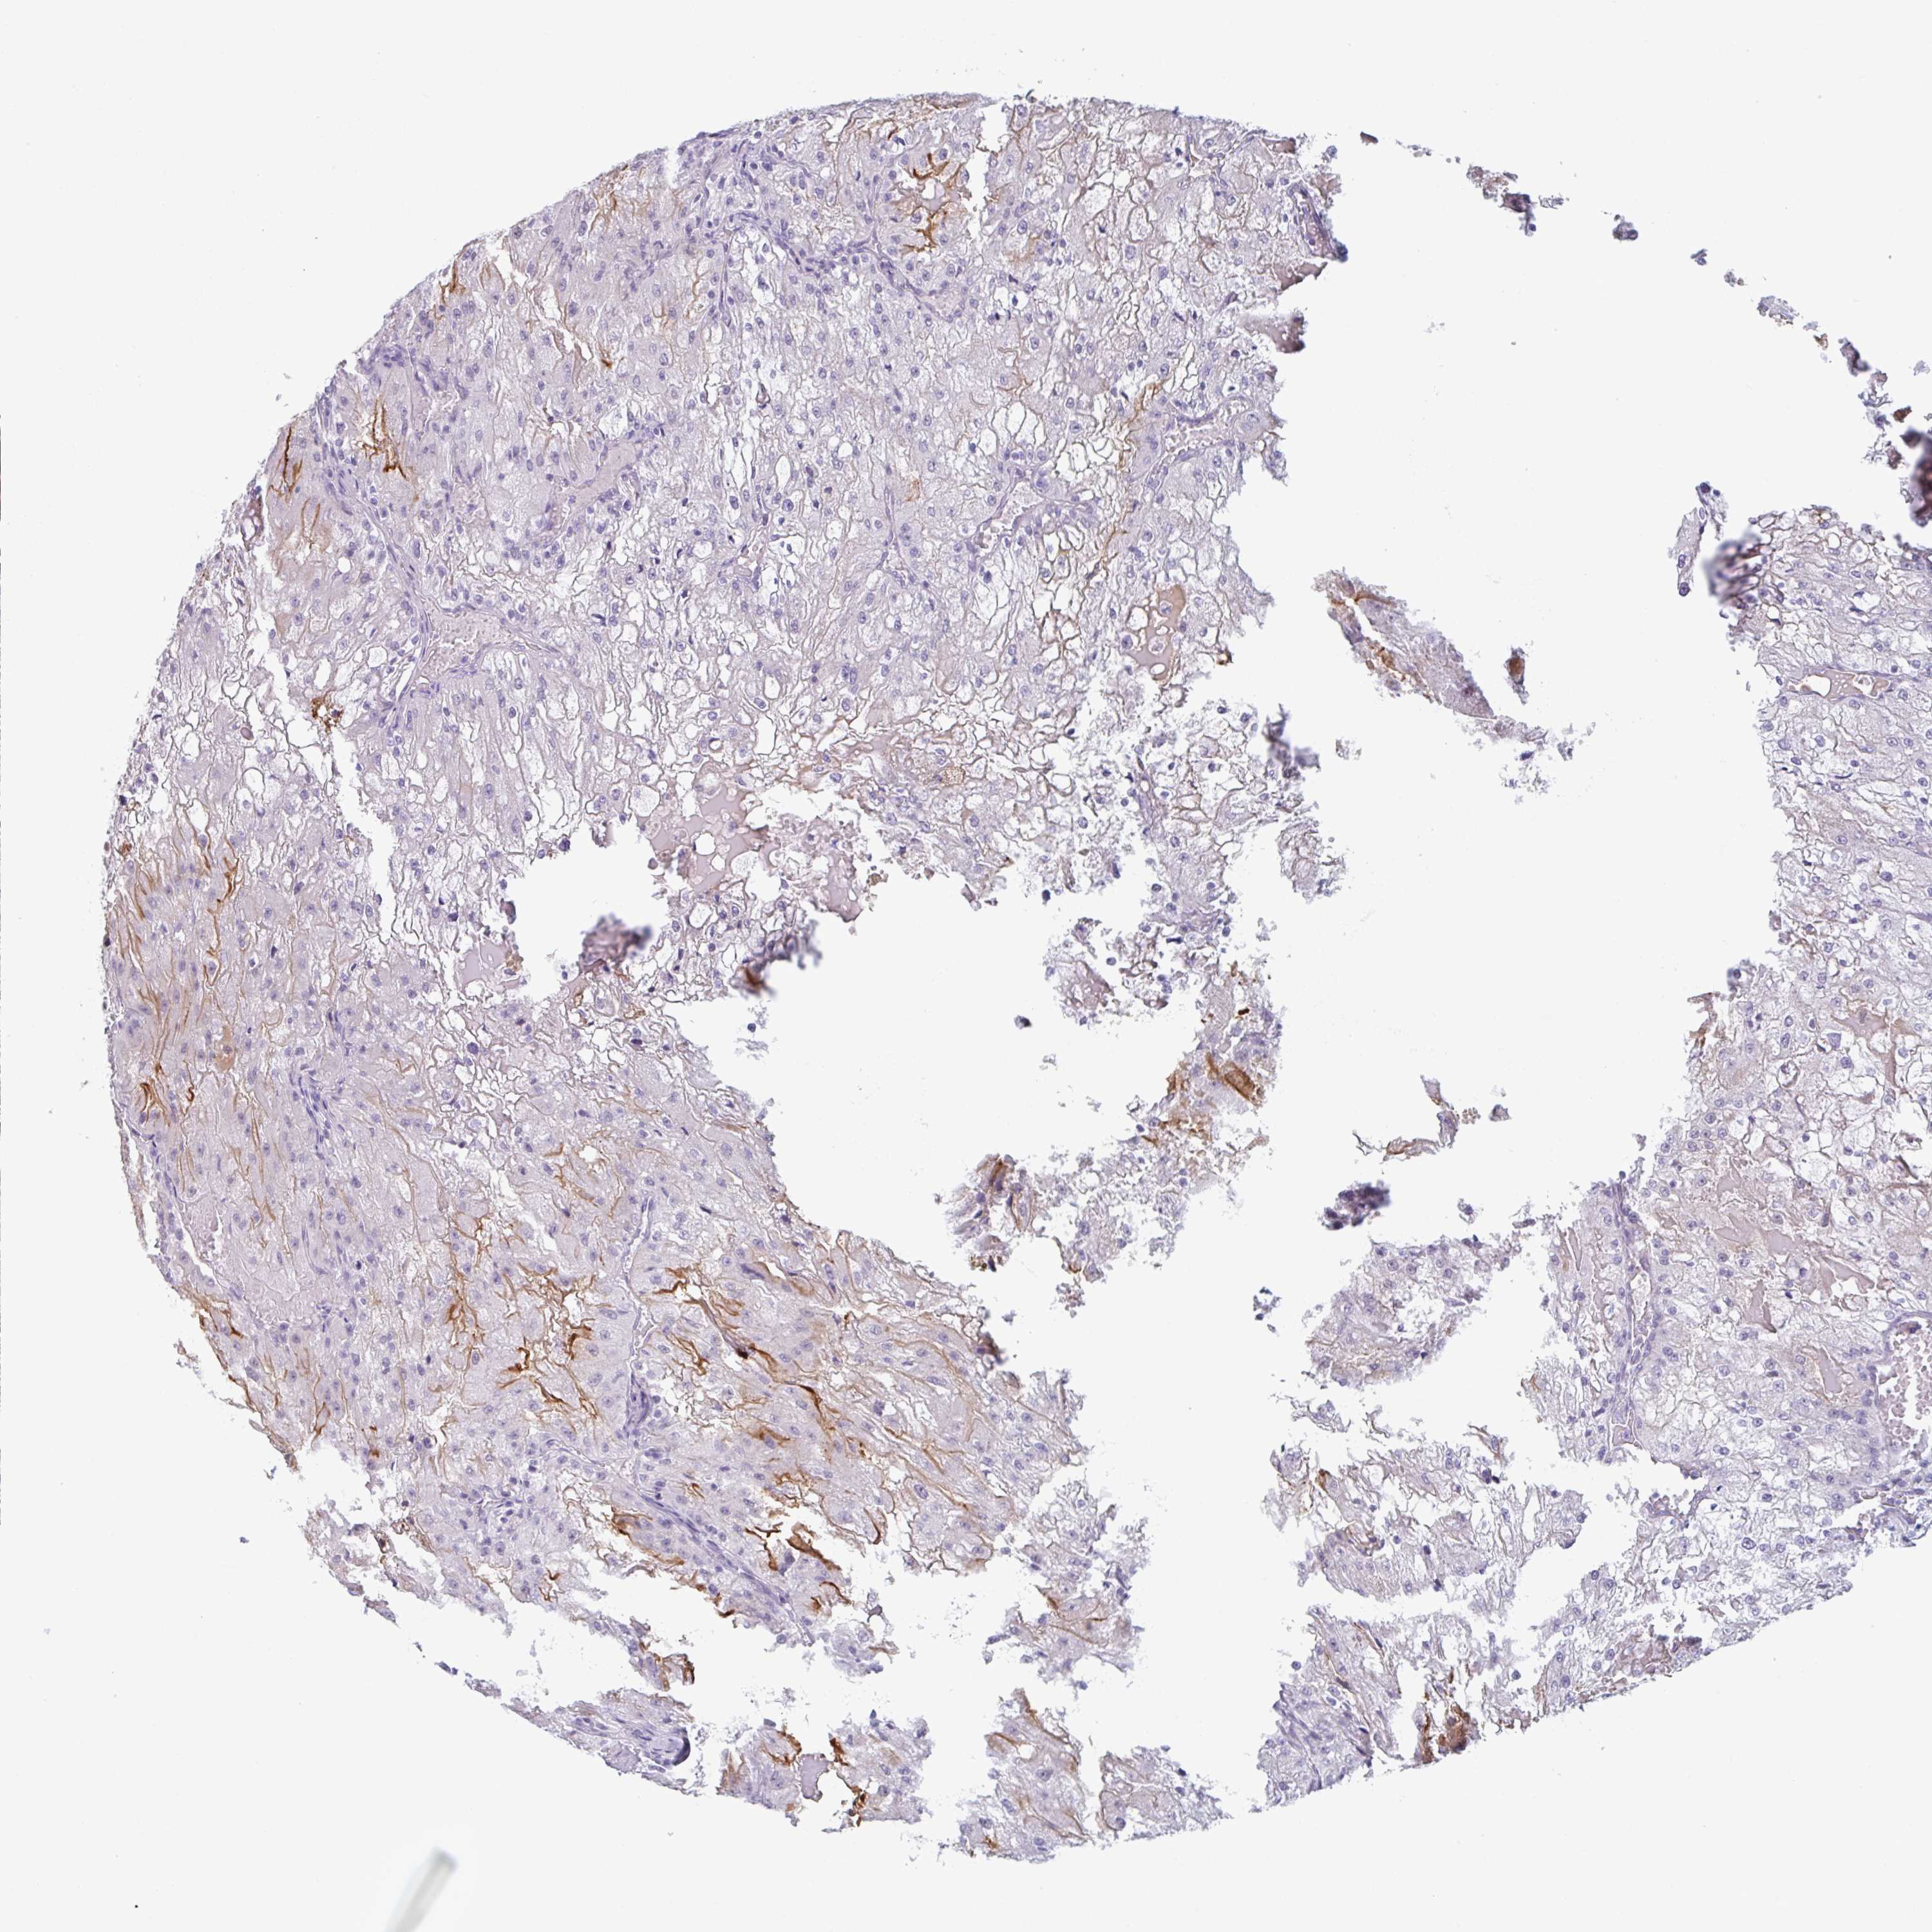

KIDNEY RENAL CLEAR CELL CARCINOMA (VALIDATION) - Interactive survival scatter ploti

The Survival Scatter plot shows the clinical status (i.e. dead or alive) for all individuals in the patient cohort, based on the same data that underlies the corresponding Kaplan-Meier plots. Patients that are alive at last time for follow-up are shown in blue and patients who have died during the study are shown in red.

The x-axis shows the expression levels (FPKM) of the investigated gene in the tumor tissue at the time of diagnosis. The y-axis shows the follow-up time after diagnosis (years). Both axes are complimented with kernel density curves demonstrating the data density over the axes. The top density plot shows the expression levels (FPKM) distribution among dead (red) and alive patients (blue). The right density plot shows the data density of the survived years of dead patients with high and low expression levels respectively, stratified using the cutoff indicated by the vertical dashed line through the Survival Scatter plot. This cutoff is automatically defined based on the FPKM cutoff that minimizes the p-score. The cutoff can be changed by dragging the vertical line or by entering a cutoff value in the square labeled "Current cut-off".

Under the Survival Scatter plot the p-score landscape (black curve; left axis) is shown together with dead median separation (red curve; right axis). Dead median separation is the difference in median mRNA expression between patients who have died with high and low expression, respectively. It is calculated as follows: median FPKM expression of dead patients with high expression - median FPKM expression of dead patients with low expression. This is intended to aid the user in visually exploring custom cutoffs and the associated p-scores and dead median separation.

Individual patient data is displayed and can be filtered by clicking on one or more of the category buttons on the top of the page. Categories describing expression level and patient information include: high, low, alive, dead, female, male and tumor stages. The scale of the x-axis can be toggled between linear and log-scale by clicking on the "x log" button. Mouse-over function shows TCGA ID, patient information and mRNA expression (FPKM) for each patient.

& Survival analysisi

Kaplan-Meier plots summarize results from analysis of correlation between mRNA expression level and patient survival. Patients were divided based on level of expression into one of the two groups "low" (under cut off) or "high" (over cut off). X-axis shows time for survival (years) and y-axis shows the probability of survival, where 1.0 corresponds to 100 percent.

PLG is not prognostic in Kidney Renal Clear Cell Carcinoma (validation)

Best expression cut offi

Based on the FPKM value of each gene, patients were classified into two groups and association between prognosis (survival) and gene expression (FPKM) was examined. The best expression cut-off refers the FPKM value that yields maximal difference with regard to survival between the two groups at the lowest log-rank P-value. Best expression cut-off was selected based on survival analysis .

When clicking on this number, the vertical dashed line indicating cut-off, the interactive survival plot, and the Kaplan-Meier curve will be adjusted to show results based on the best expression cut-off.

: 0.86

Average pTPM 15.6

Number of samples 100